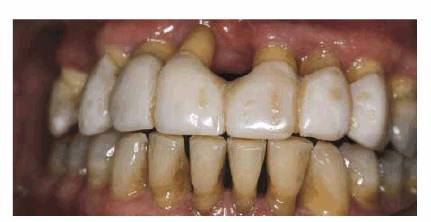

In instances where the patient has had posterior bite collapse and advanced

rehabilitation. Such a case is illustrated in Figures 23-19A, 23-19B, 23-19C, 23-19D, 23-19E, 23-19F and G, and 23-19H and I using interim bonding followed by a telescopic

Figure 23-19A: This 65-year-old man was embarrassed by the appearance of his front teeth.

Figure 23-19B: Using the principles previously outlined in this chapter, composite resin bonding was done to immediately improve the patient's appearance and stabilize the dentition.

Figure 23-19C: Following periodontal therapy and interim stabilization for 3 months, a maxillary telescopic prosthesis was constructed. The gold copings are seen here on the model.

Figure 23-19D: The superstructure was constructed in two sections using a semiprecision attachment.

Figure 23-19E: The gold copings are seen here cemented in the mouth with final cement. This permits the superstructure to be cemented with soft cement so that it can be easily removed in the event that repairs are necessary. A further advantage in using "individual" telescopic copings is that the patient will require only minimal treatment if there is a superstructure cement washout.

Figure 23-19F and G: The superstructure was first cemented with petrolatum and zinc oxide for 1 week to help fully seat the case.

Figure 23-19H and I: Before and after treatment comparison show a greatly improved esthetic result. Note the patient's lower lip line. He felt comfortable that, because of his low lip line, none of the exposed metal margins would show.